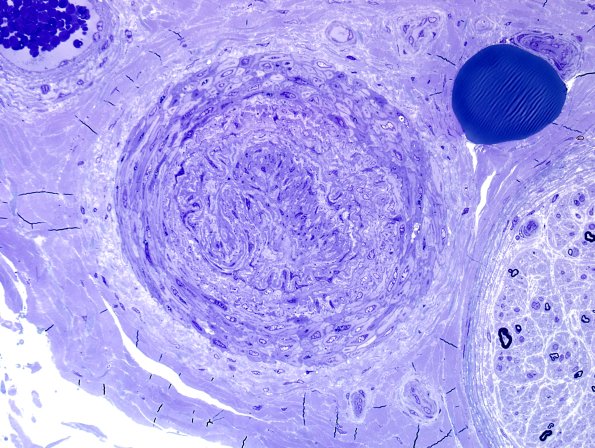

Washington University Experience | PERIPHERAL NEUROPATHY | 0 PNS ARTIFACTS | 10D Vessel, telescoped Plastic 1.jpg

Plastic sections demonstrating the artifactual nature of these telescoped vessels. (Toluidine blue stained one micron thick plastic embedded sections)